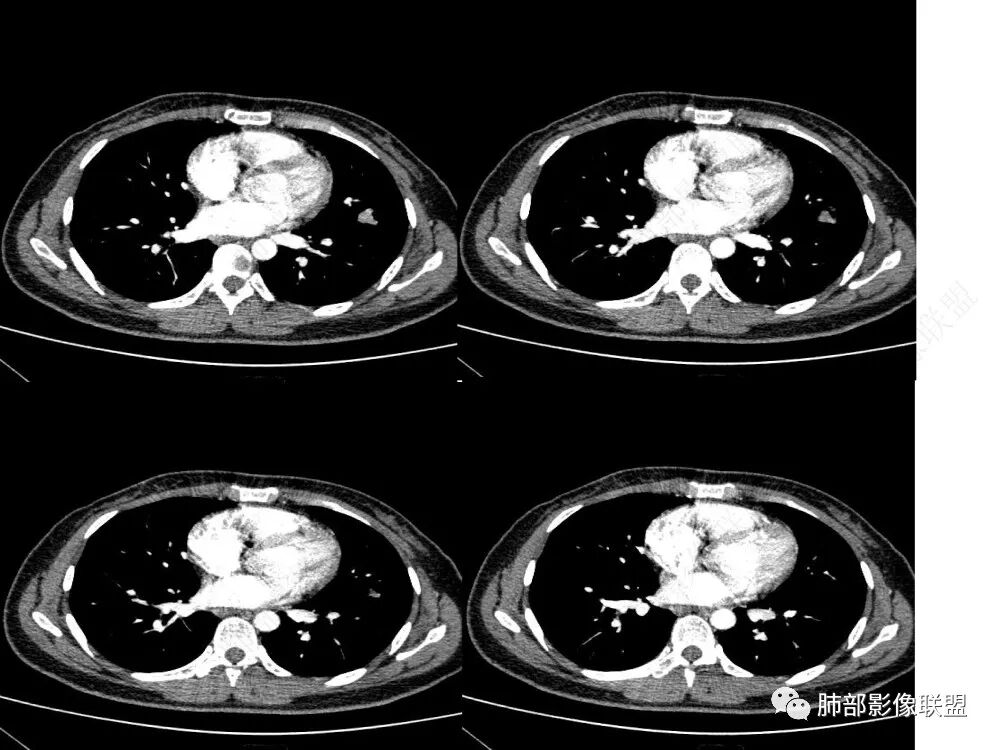

1、临床特点:30岁女性,体检发现肺部结节。

2、影像特点:左肺上叶舌段实性密度结节,边界清楚,略呈不规则三角形,边缘多平直,未见分叶、毛刺及明显收缩。密度均匀,未见钙化、脂肪密度或低密度液化空洞,持续渐进强化。未显示相关支气管及血管出入、血管贴边等。未见明确卫星病灶。双肺门及纵隔未见增大淋巴结。

3、病例小结:年轻女性,体检发现,左肺上叶舌段实性结节,边缘清楚光滑,未见分叶毛刺及收缩,亦未见边界清晰的磨玻璃晕,与支气管血管了无瓜葛等,较为符合的是肺良性结节。

3)边界清楚,未显示相关支气管及血管出入,强化明显,应当想到硬化性肺细胞瘤。

CT:形态:圆形或椭圆形结节,边界清楚,无分叶及毛刺、无胸膜凹陷征及血管集中等恶性征象,无卫星病灶,周围无纹理增多及粘连等;大小:平均直径3cm,从<1cm到>10cm均有报道;密度:均匀、软组织密度,偶有出血、囊变、钙化;强化方式:多为均匀明显强化,少数不均匀强化;其它特殊征象:血管贴边征 、空气半月征 、晕征,偶见纵隔淋巴结肿大。